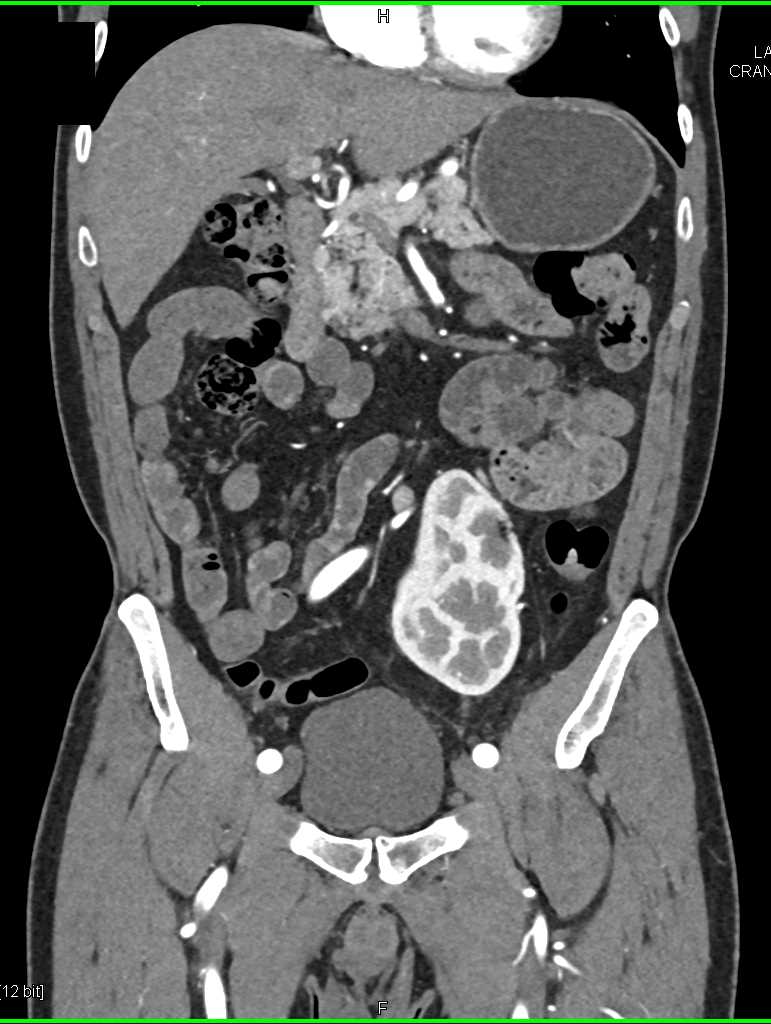

High Density Left Renal Cyst